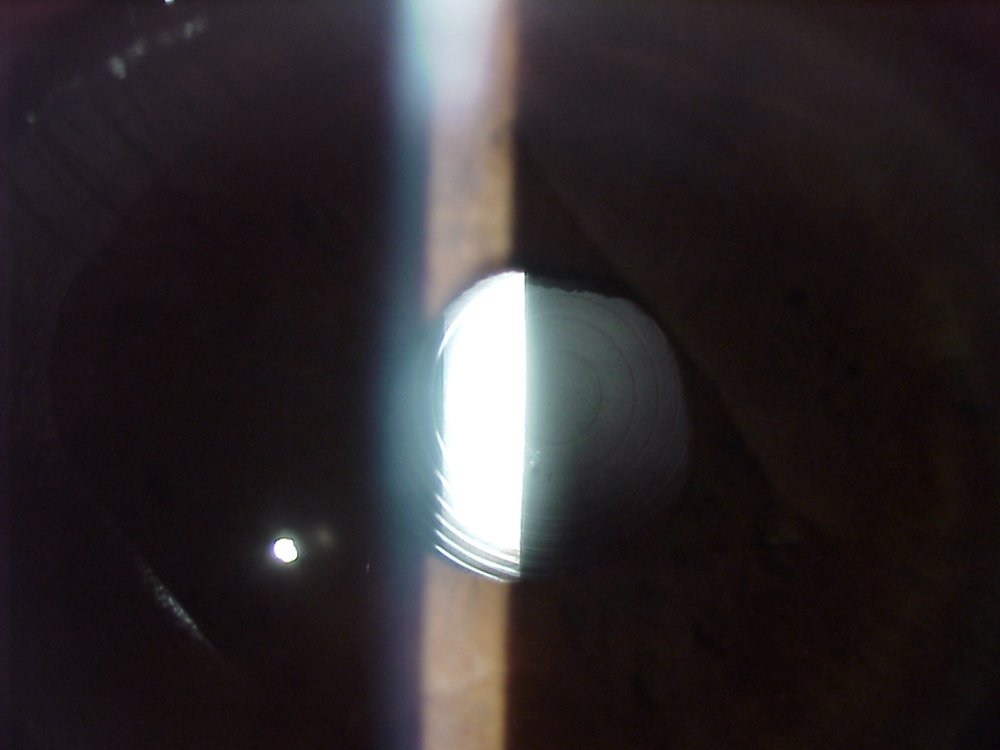

Dr. Donnenfeld said he’s been interested in improving presbyopic IOL outcomes for the last 20 years, and for 18 of them, he ignored the contribution of the vitreous. “What I have learned subsequently is that the vitreous absolutely plays a significant role in patient quality of vision. And doing optical vitrectomies to improve quality of vision has been one of the greatest advances that I’ve seen in improving patient happiness and quality of vision with presbyopic IOLs.” Dr. Donnenfeld said he will wait a minimum of 3 months and optimally 6 months before referring for an optical vitrectomy for a patient who describes a blob moving across their line of vision. “What I hope is that blob will settle and move out of the visual axis, which does happen a lot. I encourage patients to wait 6 months when possible before I refer. And one of the caveats is that if I’m going to have the patient have an optical vitrectomy, I always do a YAG capsulotomy first.”